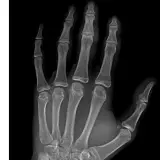

Over 2,100 interactive radiology cases, curated by radiologists for your level of training. Scroll, window, and view cases full screen — just like on PACS. Click linked findings in each writeup to jump straight to them on the image. Cases include sample reports, a focused discussion section, original illustrations, and videos.

完全交互式病例,配备您在 PACS 上期待的各项工具——滚动、调窗、缩放、平移、测量、ROI 和全屏模式。

丰富的标注直接在病例图像上突出关键发现。点击病例讲解中的关联发现,即可跳转至其在扫描上的精确位置。